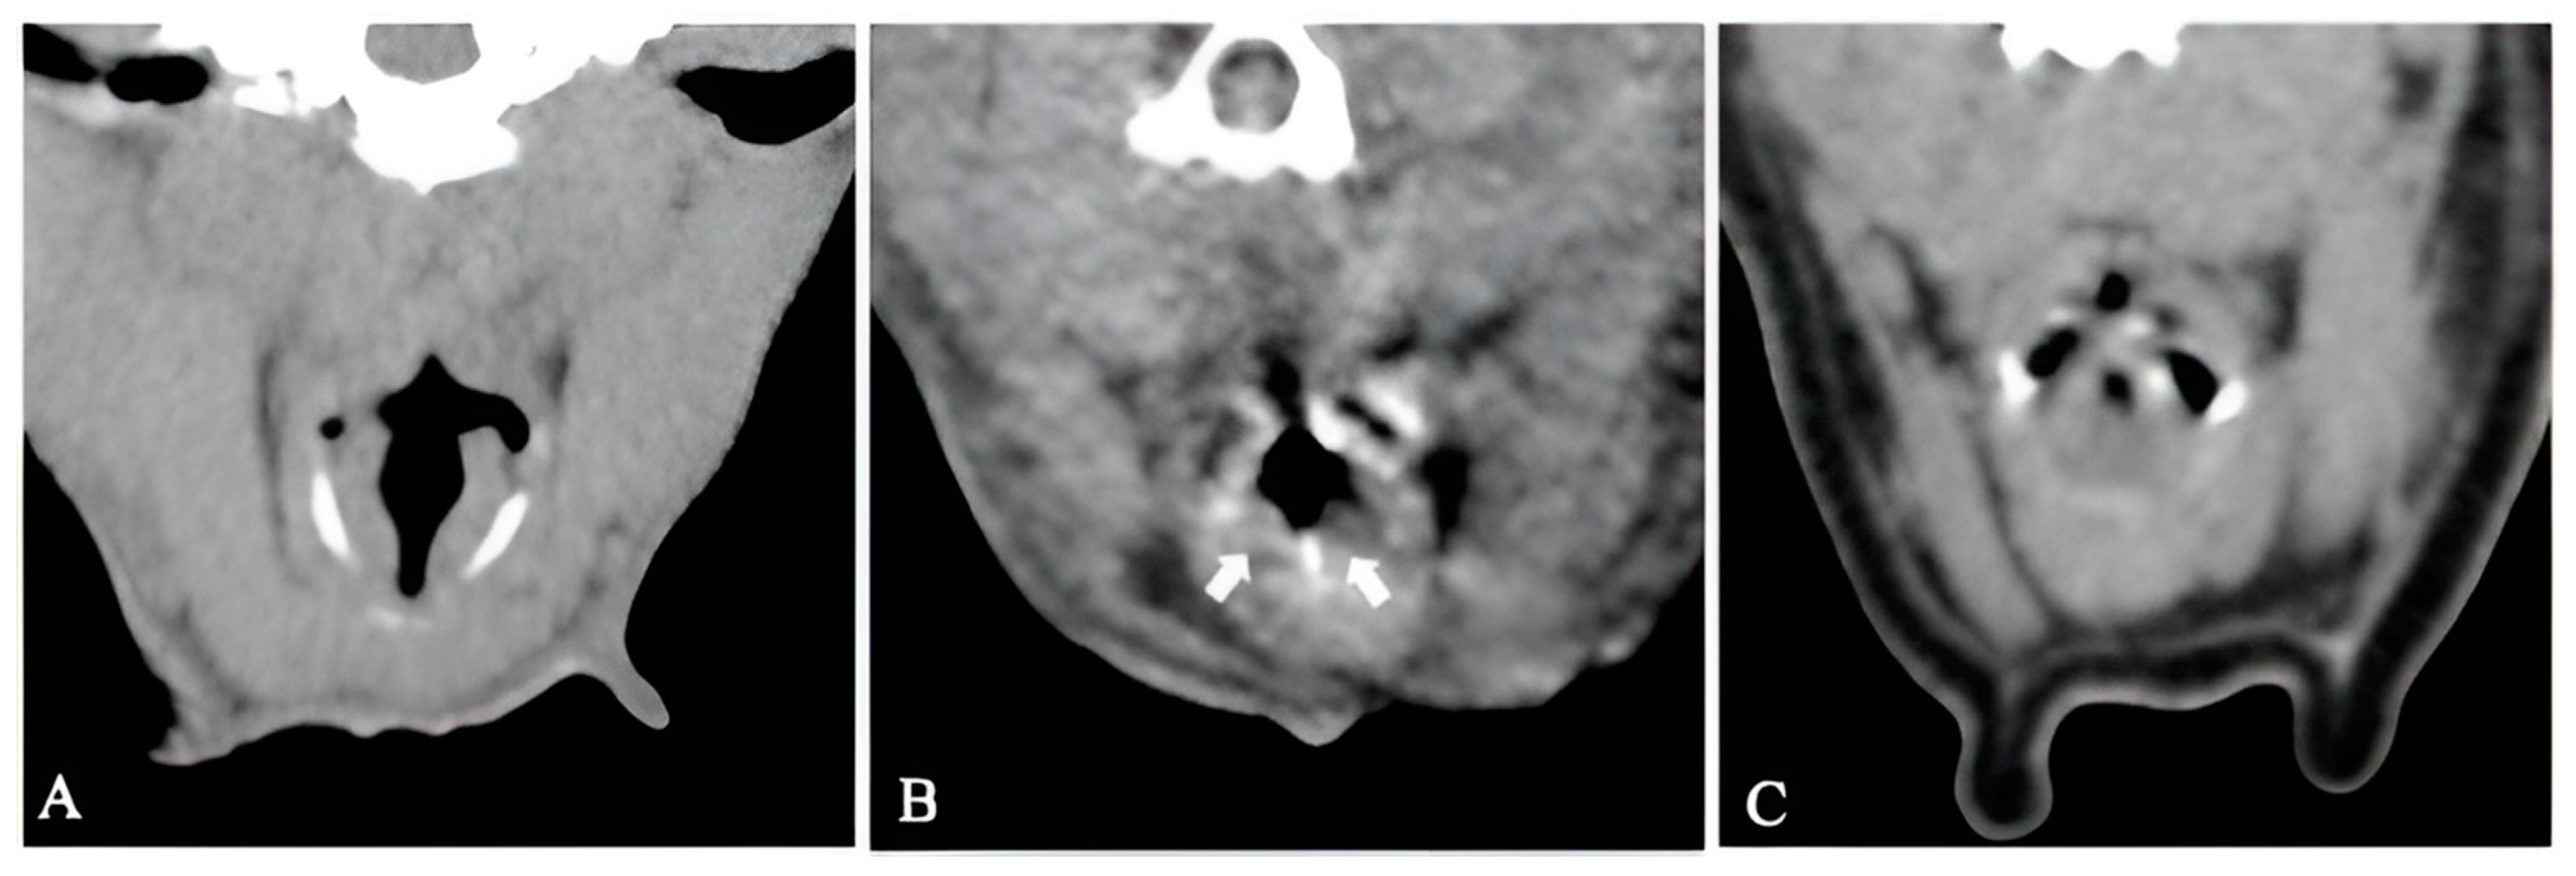

Tomographic appearance of laryngeal collapse was present in four of the seven dogs (Figure 3). Eversion of the laryngeal saccules was present in two dogs. Severe laryngeal collapse was present in two dogs (cases 3 and 15). The remaining three dogs had an open rima glottis.

Figure 3. Transverse non-contrast CT images at the level of the larynx of patients with untreated BOAS (group I). (A) Case 7, no signs of laryngeal collapse. (B) Case 6, everted laryngeal saccules. (C) Case 3, marked laryngeal collapse. White arrows: everted laryngeal saccules. Window width, 400 HU; window level 40 HU; 1 mm slice thickness.